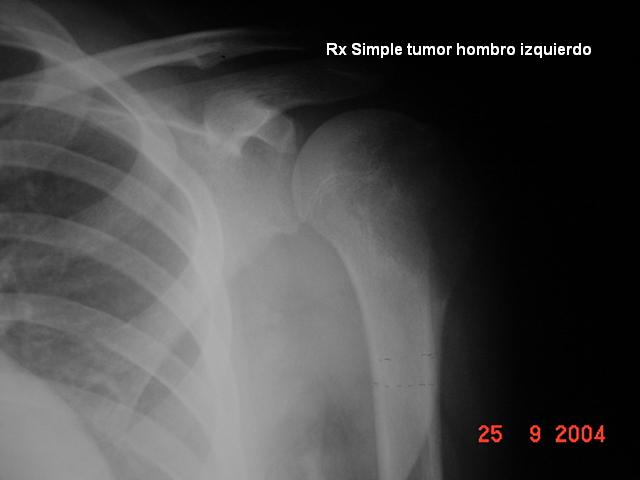

| Paciente del sexo femenino de 12 años de edad. Dolor

sobre su hombro izquierdo tratado como una tendinitis con AINES y

fisioterapia. No mejora. En una Rx simple se nota inadecuada trama de la

cabeza humeral. Se le manda una TAC. Hacemos biopsia a cielo cerrado.

RX SIMPLE TAC |